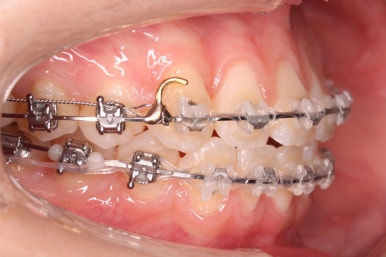

부산교정 키다리아저씨치과에서는 이번에 마이크로 임플란트라는 장치를 추가로 사용하였습니다.

잇몸뼈에 교정 치료기간동안 잠깐 사용하는 매우 작은 스크류인데요. 단단히 고정시켜 놓고, 어금니를 당겨오는데 사용합니다.

틈을 줄여주고, 어금니를 당겨오고 중앙선을 맞춰줍니다.